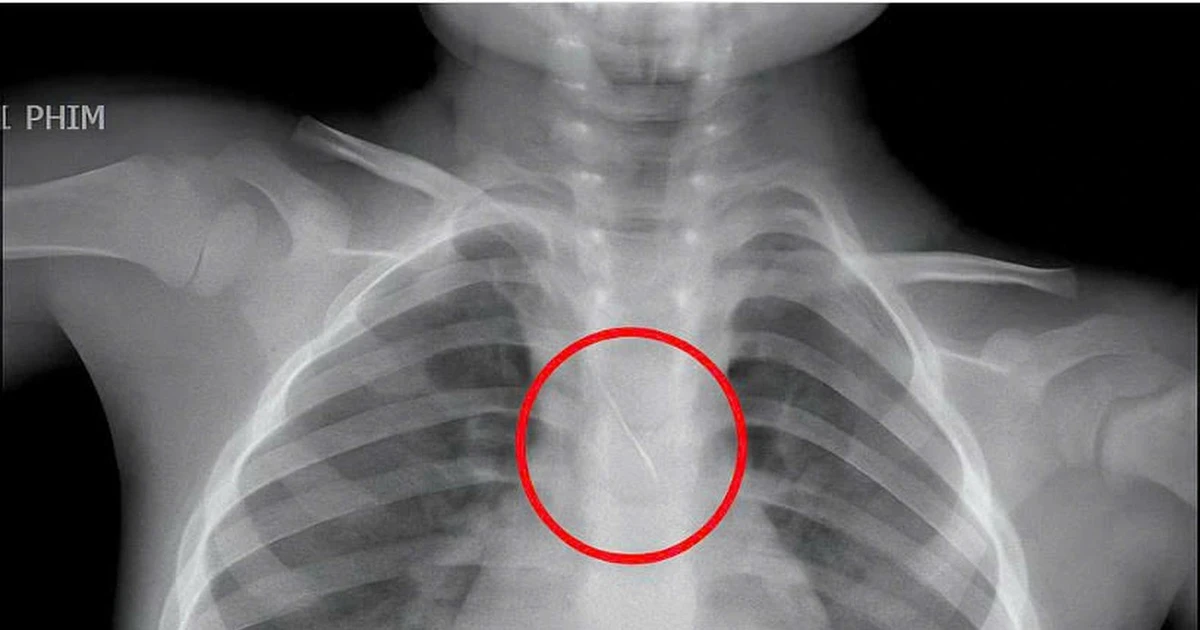

TPO - Một bé trai 3 tuổi vừa được các bác sĩ Bệnh viện Đa khoa tỉnh Quảng Trị cứu sống ngoạn mục sau khi dị vật là kim chọc tủy dài 22 mm rơi vào đường thở trong lúc làm răng, gây ho sặc dữ dội và đe dọa tắc nghẽn khí quản.